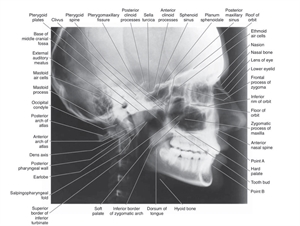

Lateral Cephalogram x-ray

A lateral cephalogram is an x-ray that covers one side of the entire face. In other words, it is the x-ray of a side profile of a person. A dentist can see most of the the facial bones from this view, including the maxilla (upper jaw) and the mandible (lower jaw). The three types of dentists that can commonly prescribe a LC are orthodontists, oral surgeons and pediatric dentists.

One of the advantages of Lateral cephalogram is that it also helps in tracing the soft tissue (lips, nasal tip, chin). A LC is frequently used to understand the growth patterns of an individual. There are certain points on the Lateral cephalogram, (both skeletal and soft tissue points) which a dentist traces in order to create angles that correspond to a normal growth pattern. Any variations in those angles apart from the normal variations can help the dentist (the orthodontist in most cases) to determine the growth stage. This can further help in formulating a treatment plan based on the patient's age. During and after the treatment, multiple LCs can be taken in order to compare the changes in the growth pattern.

LCs are also useful in analyzing the relation between multiple structures. Dentists do this by means of studying various "planes" that they have designated between two points. The angulation between these planes helps them in studying the developmental stages.